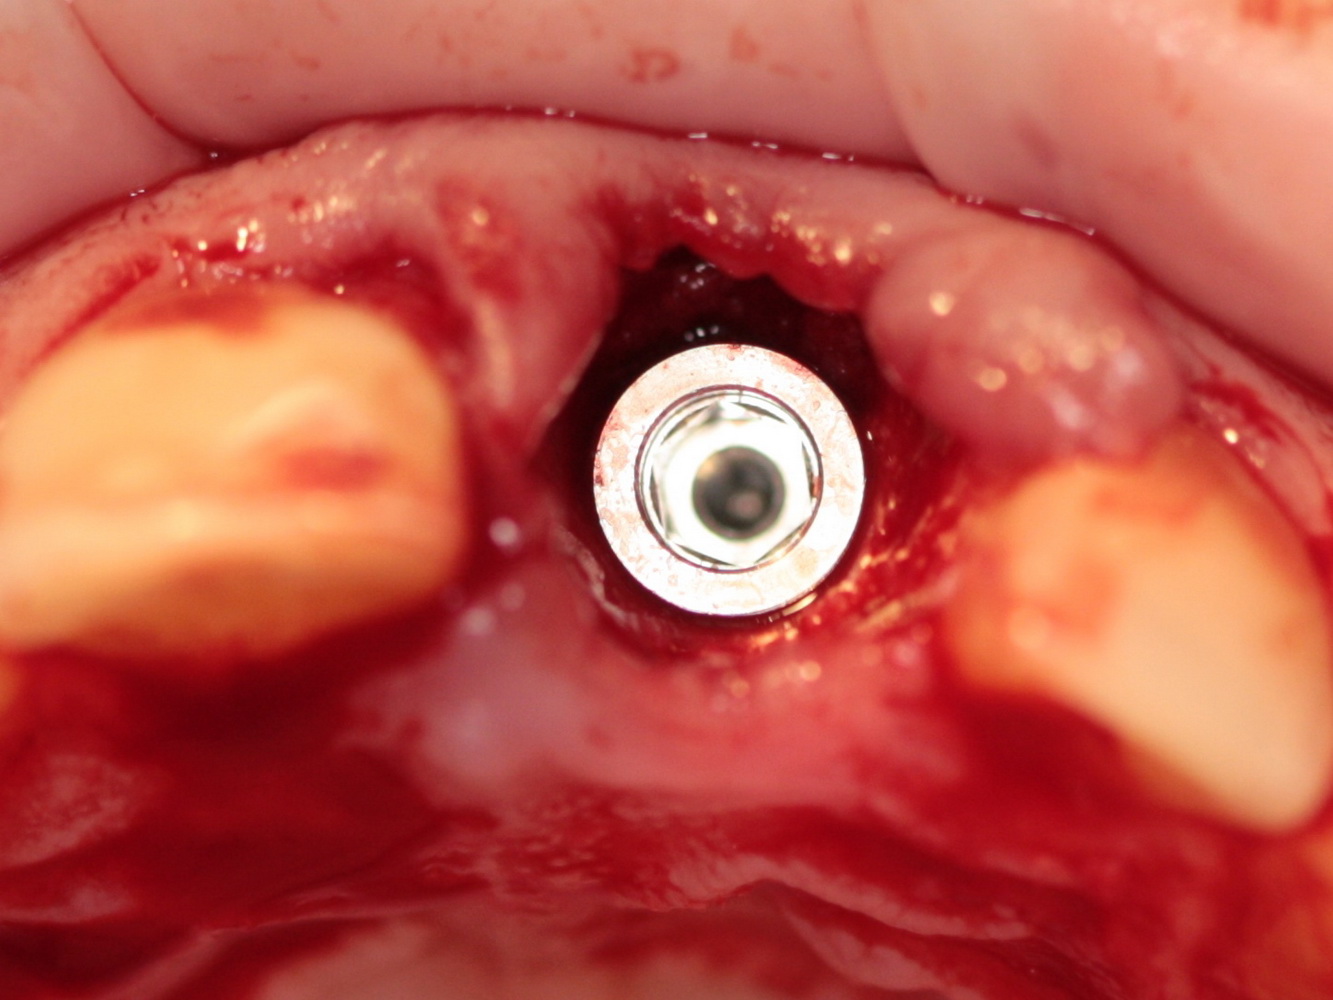

Немедленная имплантация — оптимальное решение в любой клинической ситуации